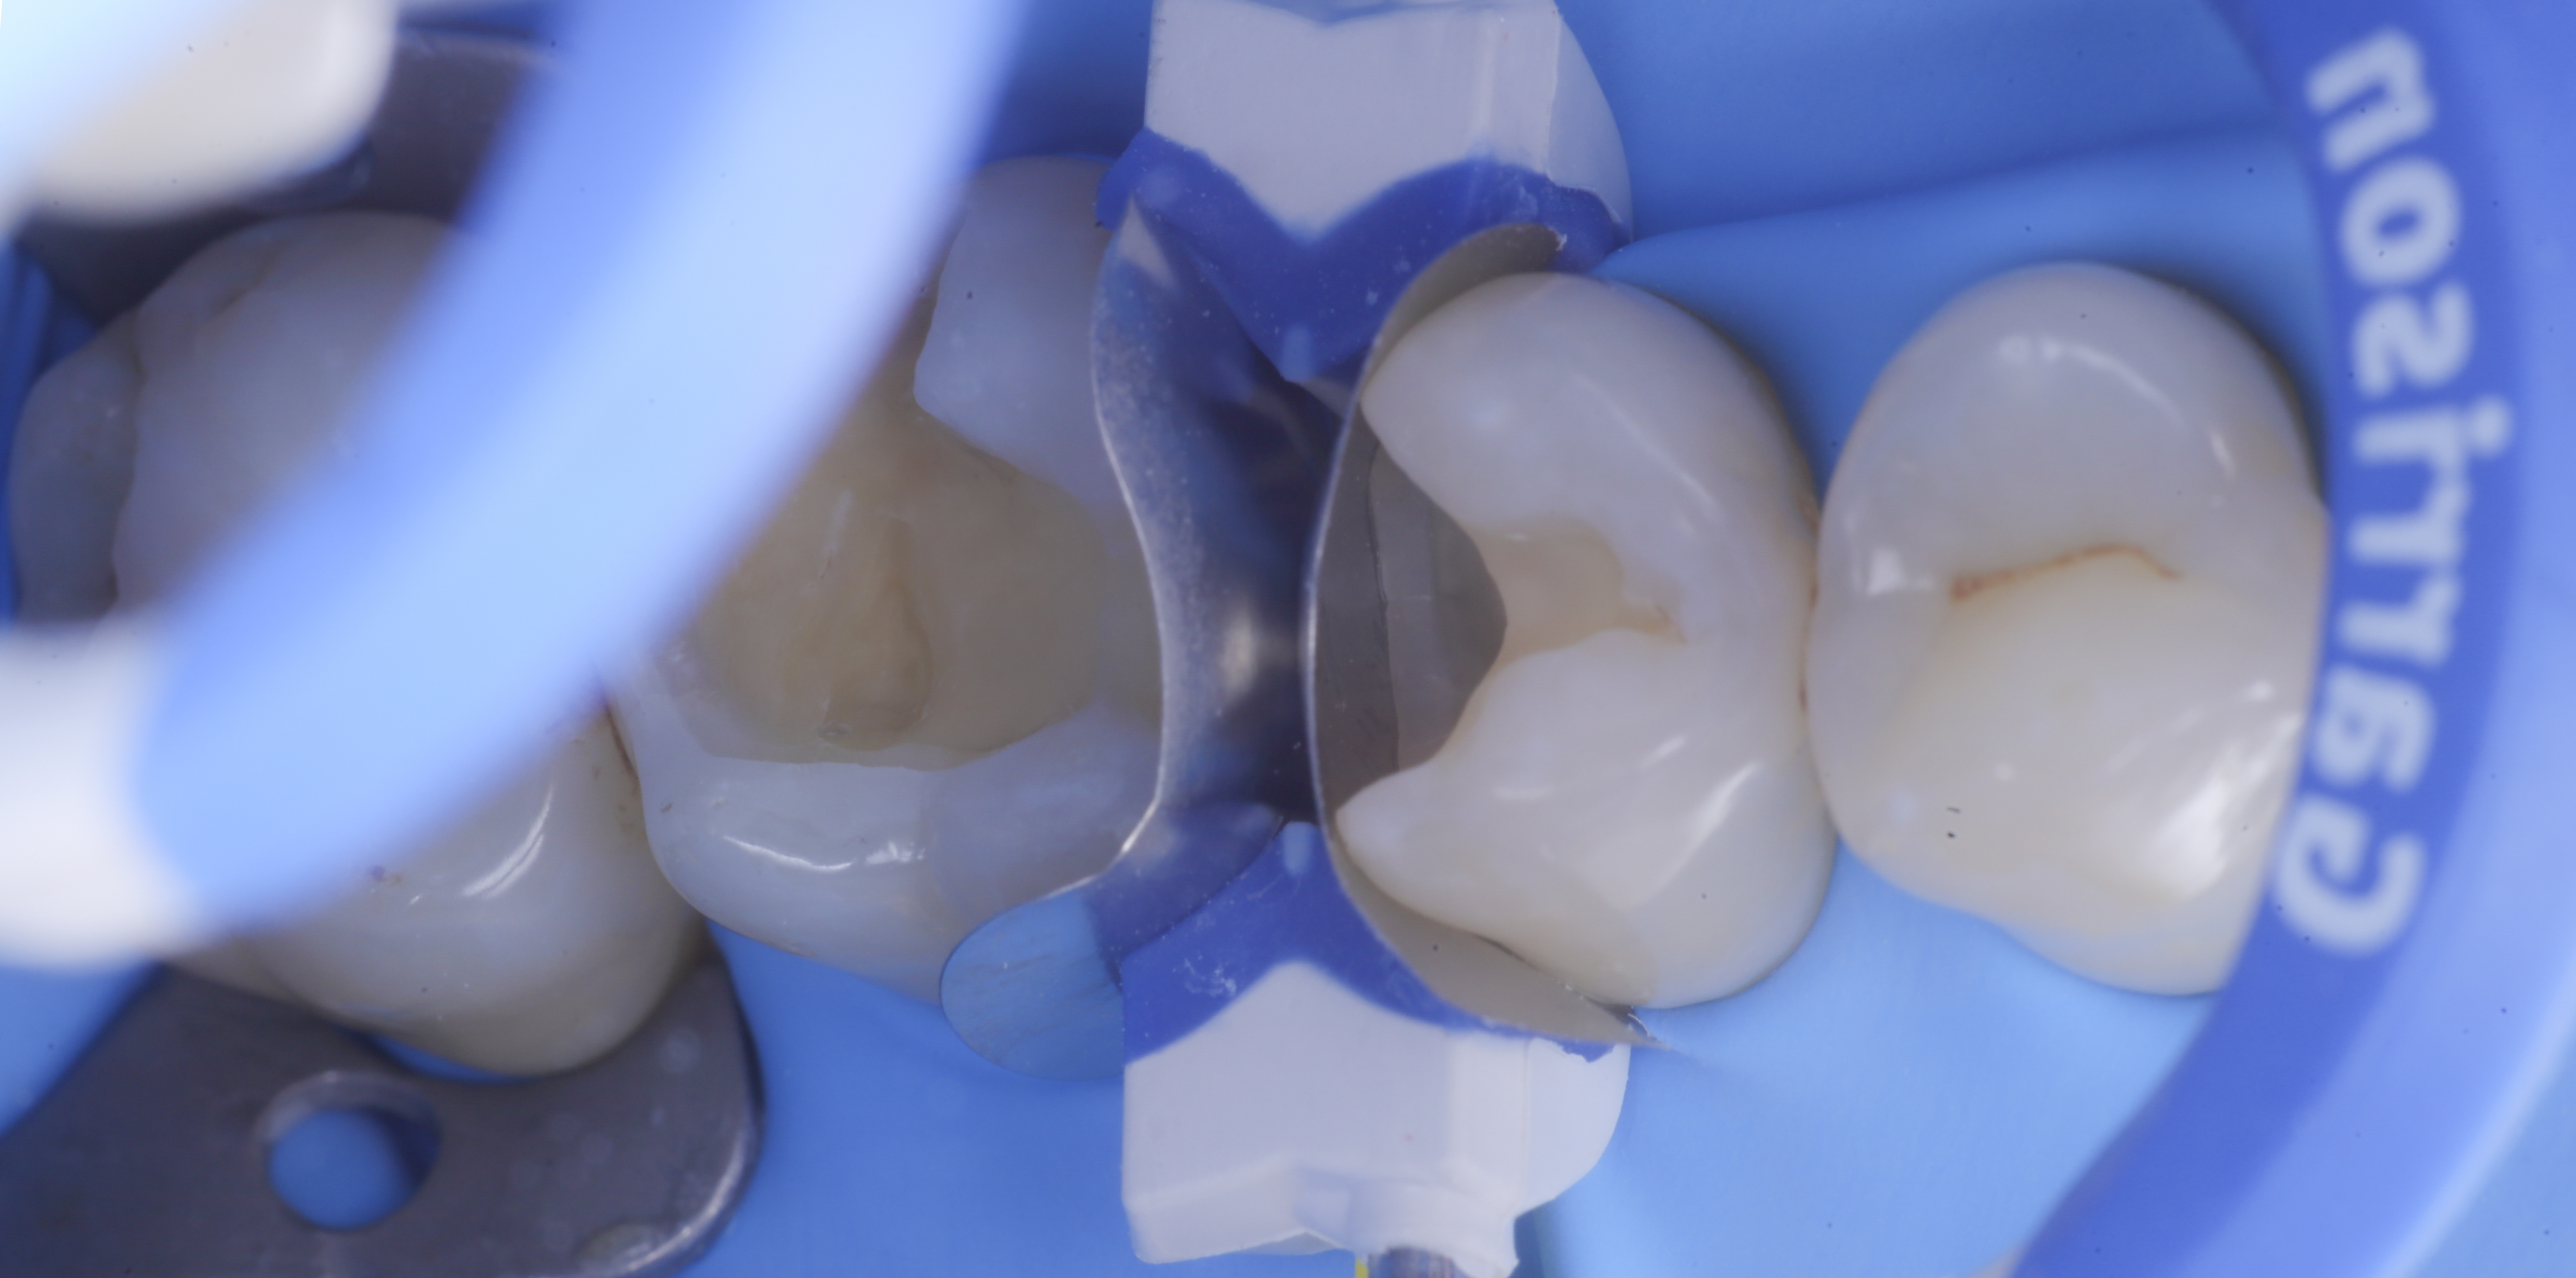

foto 4 Aspetto della chiusura cervicale e sulle pareti assiali dato dalla prima matrice

foto 5 Aspetto della chiusura cervicale e sulle pareti assiali della seconda matrice

Dopo il posizionamento del cuneo, anello e delle due matrici sezionai, selezionate per altezza e raggio di curvatura, si procede con l’applicazione dell’adesivo universale, previa pre-mordenzatura dello smalto.

A questo punto si procede con la stratificazione e modellazione di una delle due pareti inter-prossimali e si polimerizza. Si elimina quindi la matrice della parete appena eseguita sposando l’anello che viene immediatamente rialloggiato.

Successivamente, eliminato lo spessore dato dalla seconda matrice, si procede con la creazione della seconda parete.